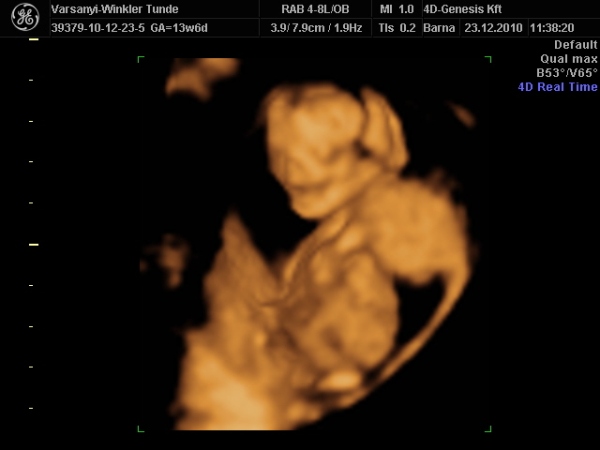

Bár tegnap a dokor bácsi azt mondta, hogy azért lassan vissza kellene vennem a lendületből, mert nem lesz jó vége. Manócska jól van, de tegnap nem tudtuk megnézni. Hasi uh-val próbálkozott, de pont úgy fordult, hogy csak a nagy kobakját láttuk

Természetesen lánynak is látszott, bár azt mondta, hogy még ne éljük bele magunkat. A férjem le is tört egy kicsit, de nem vallotta volna be.Holnap reggel megyek AFP-re.